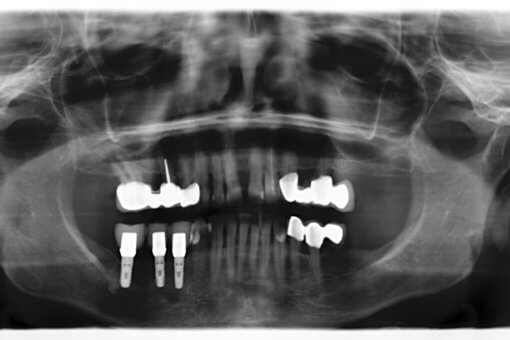

- Implantologie

- Digitales Röntgen, 3D Röntgen (DVT)